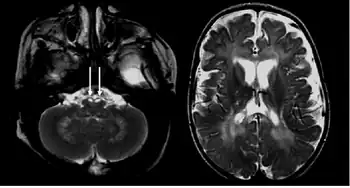

The disease may be diagnosed by its characteristic grouping of certain cells (multinucleated globoid cells), nerve demyelination and degeneration, and destruction of brain cells. Special stains for myelin (e.g., luxol fast blue) may be used to aid diagnosis.